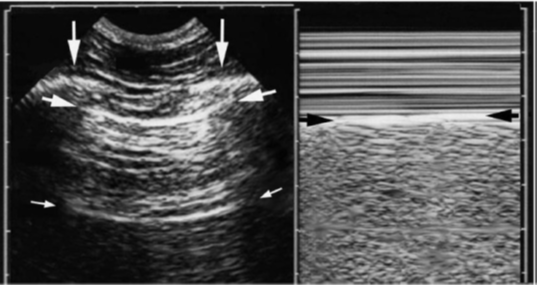

Sinal da praia (modo M)

- Parede torácica (linhas horizontais)

- Ar (imagem granulada)- “areia”

- Sinal do deslizamento do modo M

Fonte: OLIVEIRA R e colaboradores. Ultrassonografia pulmonar: uma ferramenta adicional na COVID-19. Radiologia Brasileira, 2020.

Sinal do quadrado (modo B) e Sinal do sinusoide (modo M)

No modo M, as setas pretas indicam a pleura parietal e as brancas indicam a pleura visceral. O sinal do sinusoide é indicativo de derrame pleural.